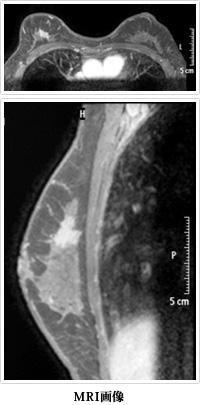

5. 乳房造影MRI検査

MRI用造影剤であるガドリニウムを使用しておこないます。

ほとんどの乳房の病気は、マンモグラフィーや乳腺エコーで特定可能であり、さらに乳房の針生検により良悪性の診断が可能です。

しかし、乳腺エコーで病変が特定できず針生検も不可能な場合、さらに画像検査と組織の病理結果が一致しない場合におこないます。

またMRIだけでしか発見出来ない多発乳がんが存在しますが、現時点でMRIだけでしか指摘できない病変の対処方法が決定しておらず、今後の検討が必要です。

手術前には、必須の検査となりつつあります。